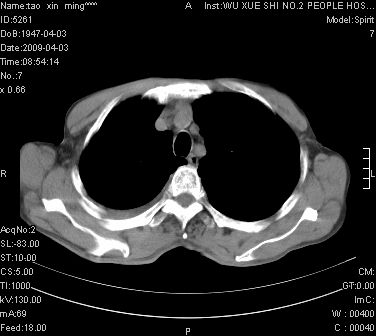

男.62.咯血.胸痛

是不是外伤的,看起来右侧肋骨骨折,右肺唑伤,右胸腔积血, 右肺背段可见一软组织肿块,边缘清晰,可以和中中央型肺ca合并

肺出血,周围型肺癌,右侧胸腔积液

明天请武大中南医院外科熊主任手术.患者无外伤.我考虑肺癌

右下周围型肺癌,右侧胸腔积。

右下周围型肺癌,右下肺出血,右侧胸腔积。

考虑肺癌并右侧胸腔积液肺出血

1)考虑右肺下叶周围型肺癌,并右肺下叶肺出血。2)右侧少量胸腔积液。

1)考虑右肺下叶周围型肺癌。2)右侧少量胸腔积液。